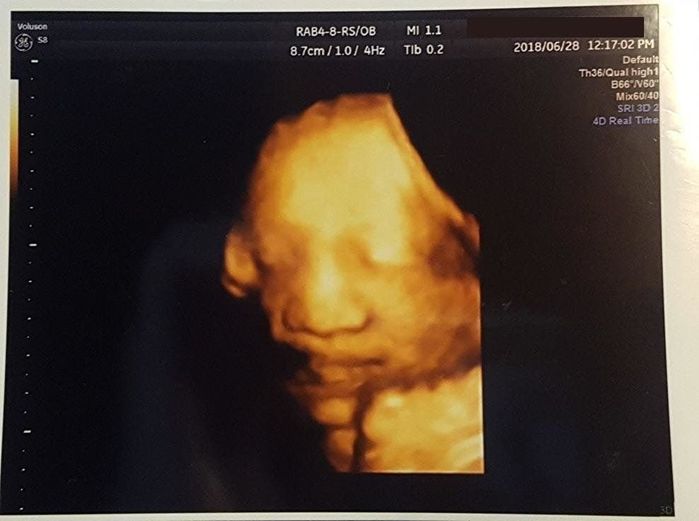

妊娠39週目 初めての4Dエコー。リアルに動いている!

4Dエコーで撮影してもらいました。この時は口の前に手を添えています。しかも、手を動かしている様子を動画で見ることもできました。この日は出産予定日の前日。子宮口が1cmしか開いていないので、出産はまだ先のようです。

推定体重は3152gで、1ヶ月前と比べると1kg近く増えています。どんどん重量感が増してきて、「大きい子が生まれるのかな…?」とドキドキしていました。